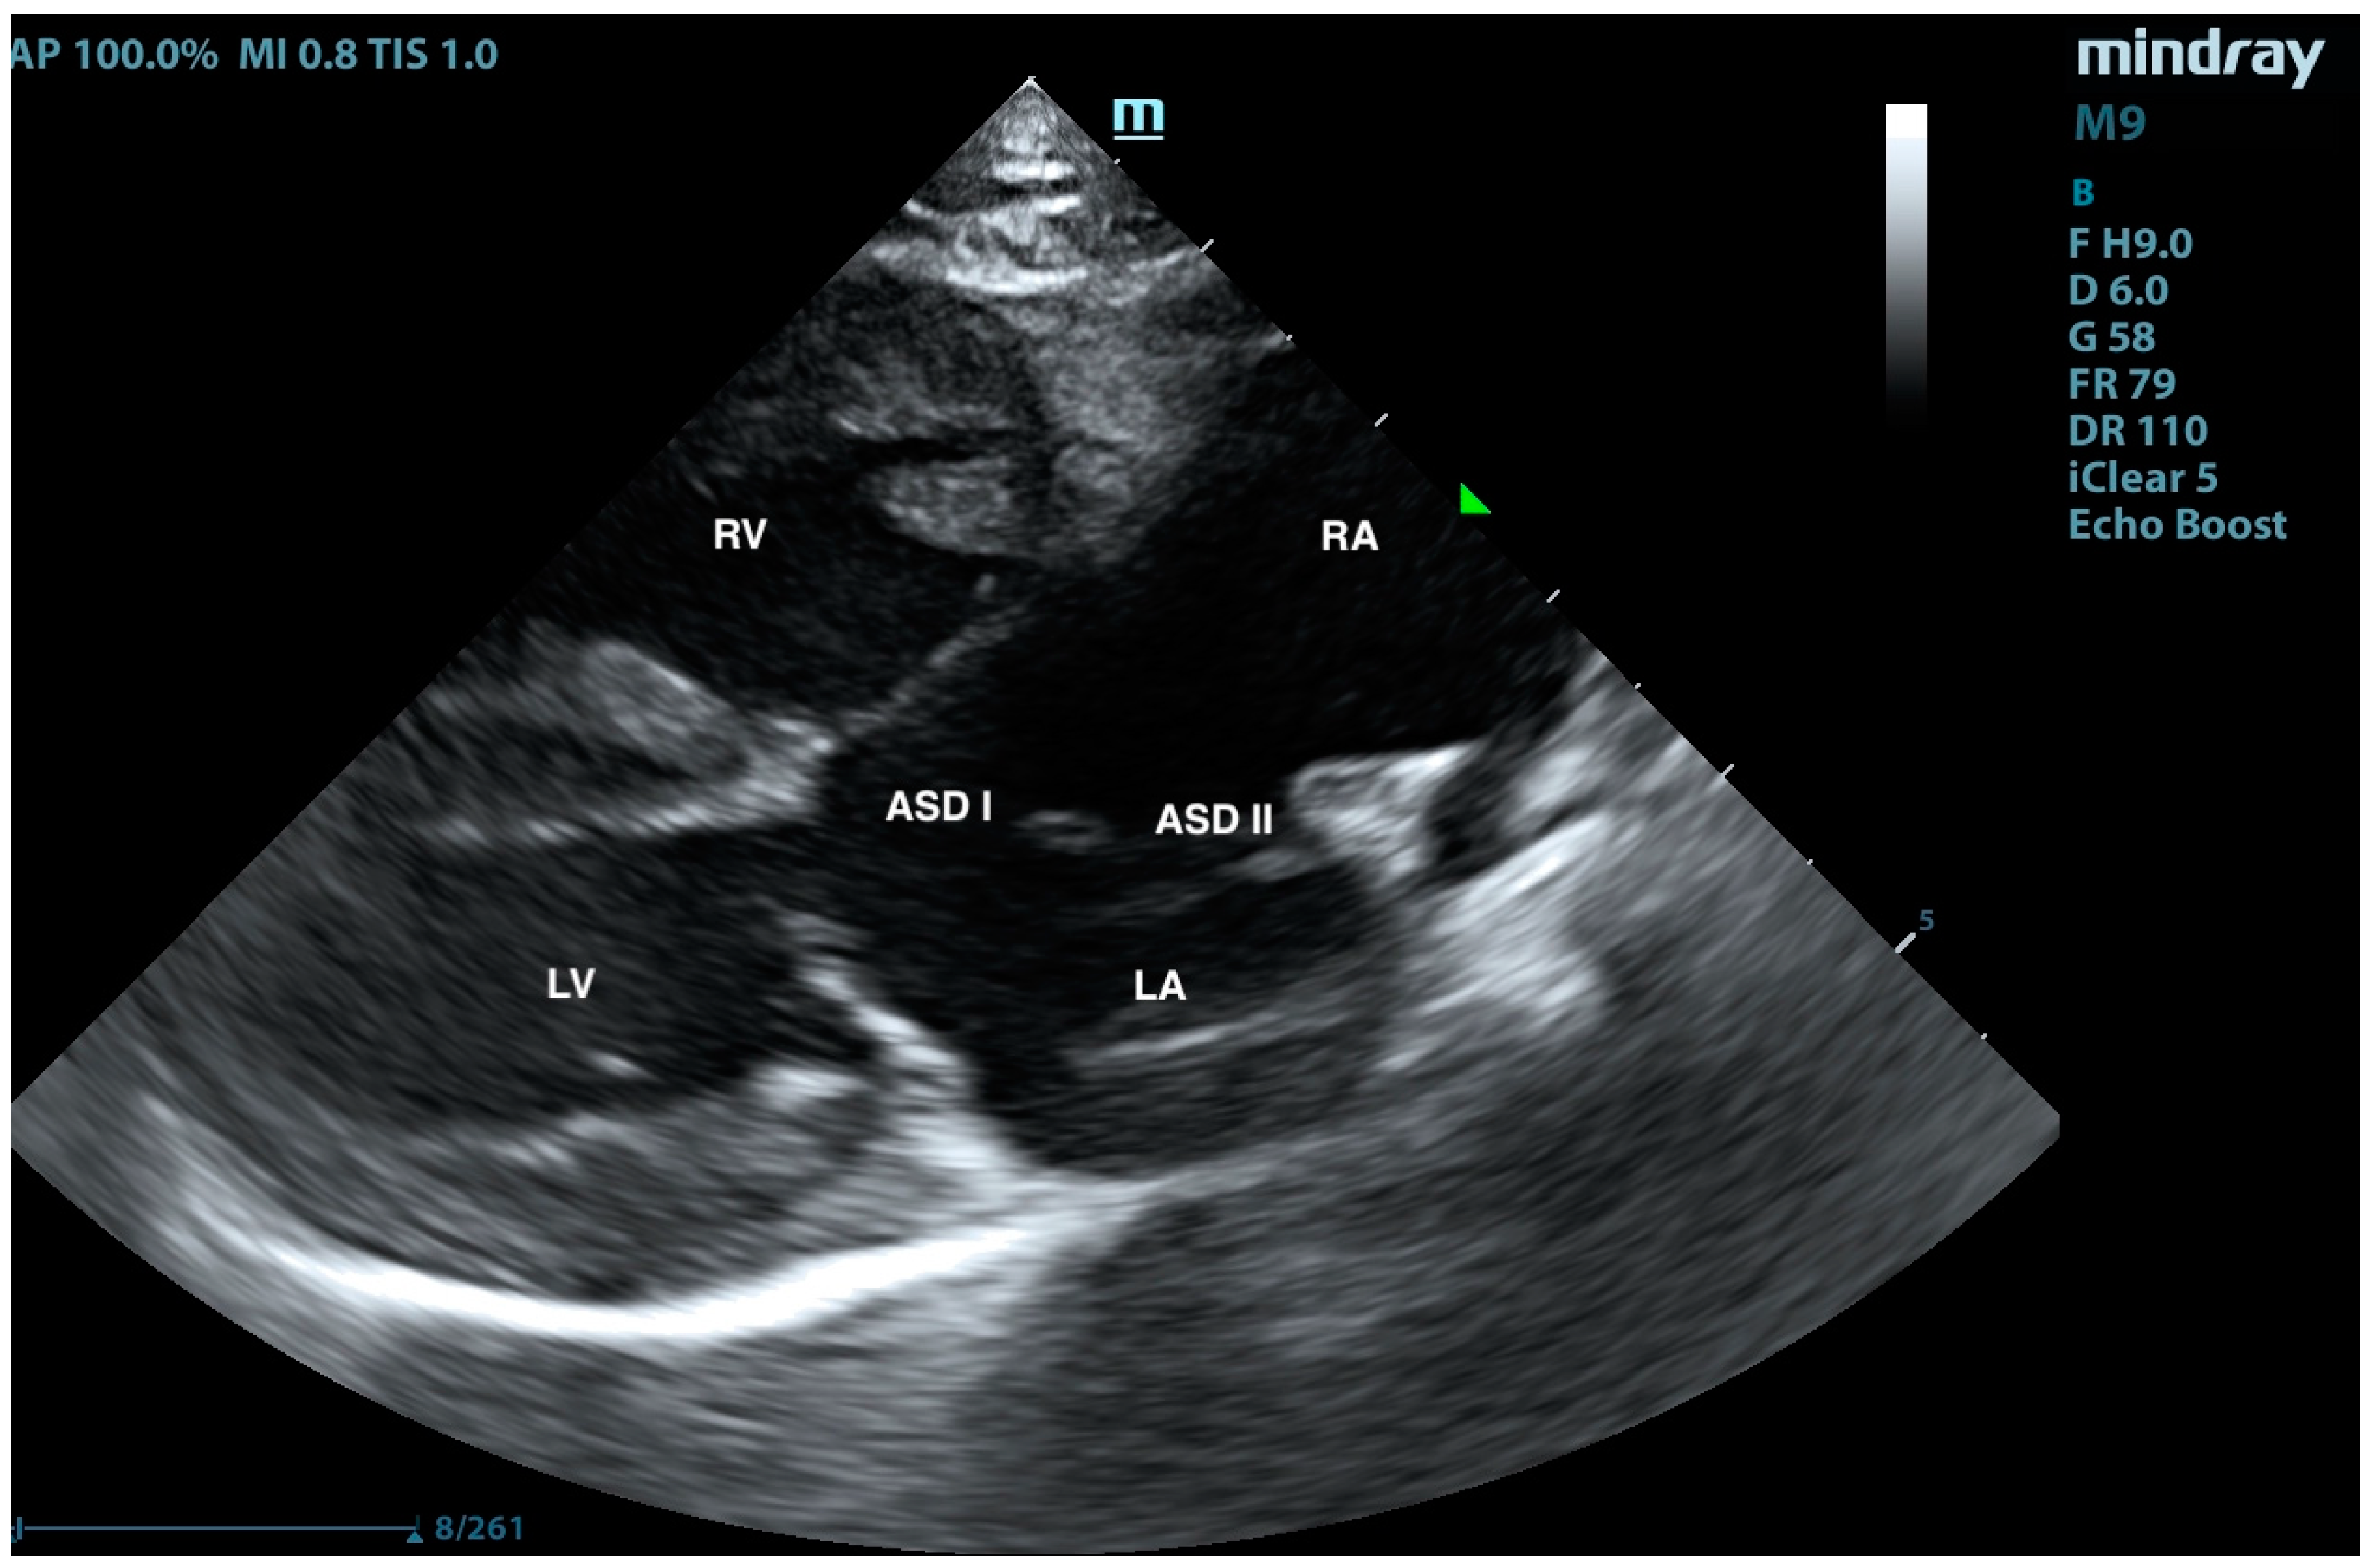

2. Case Presentation